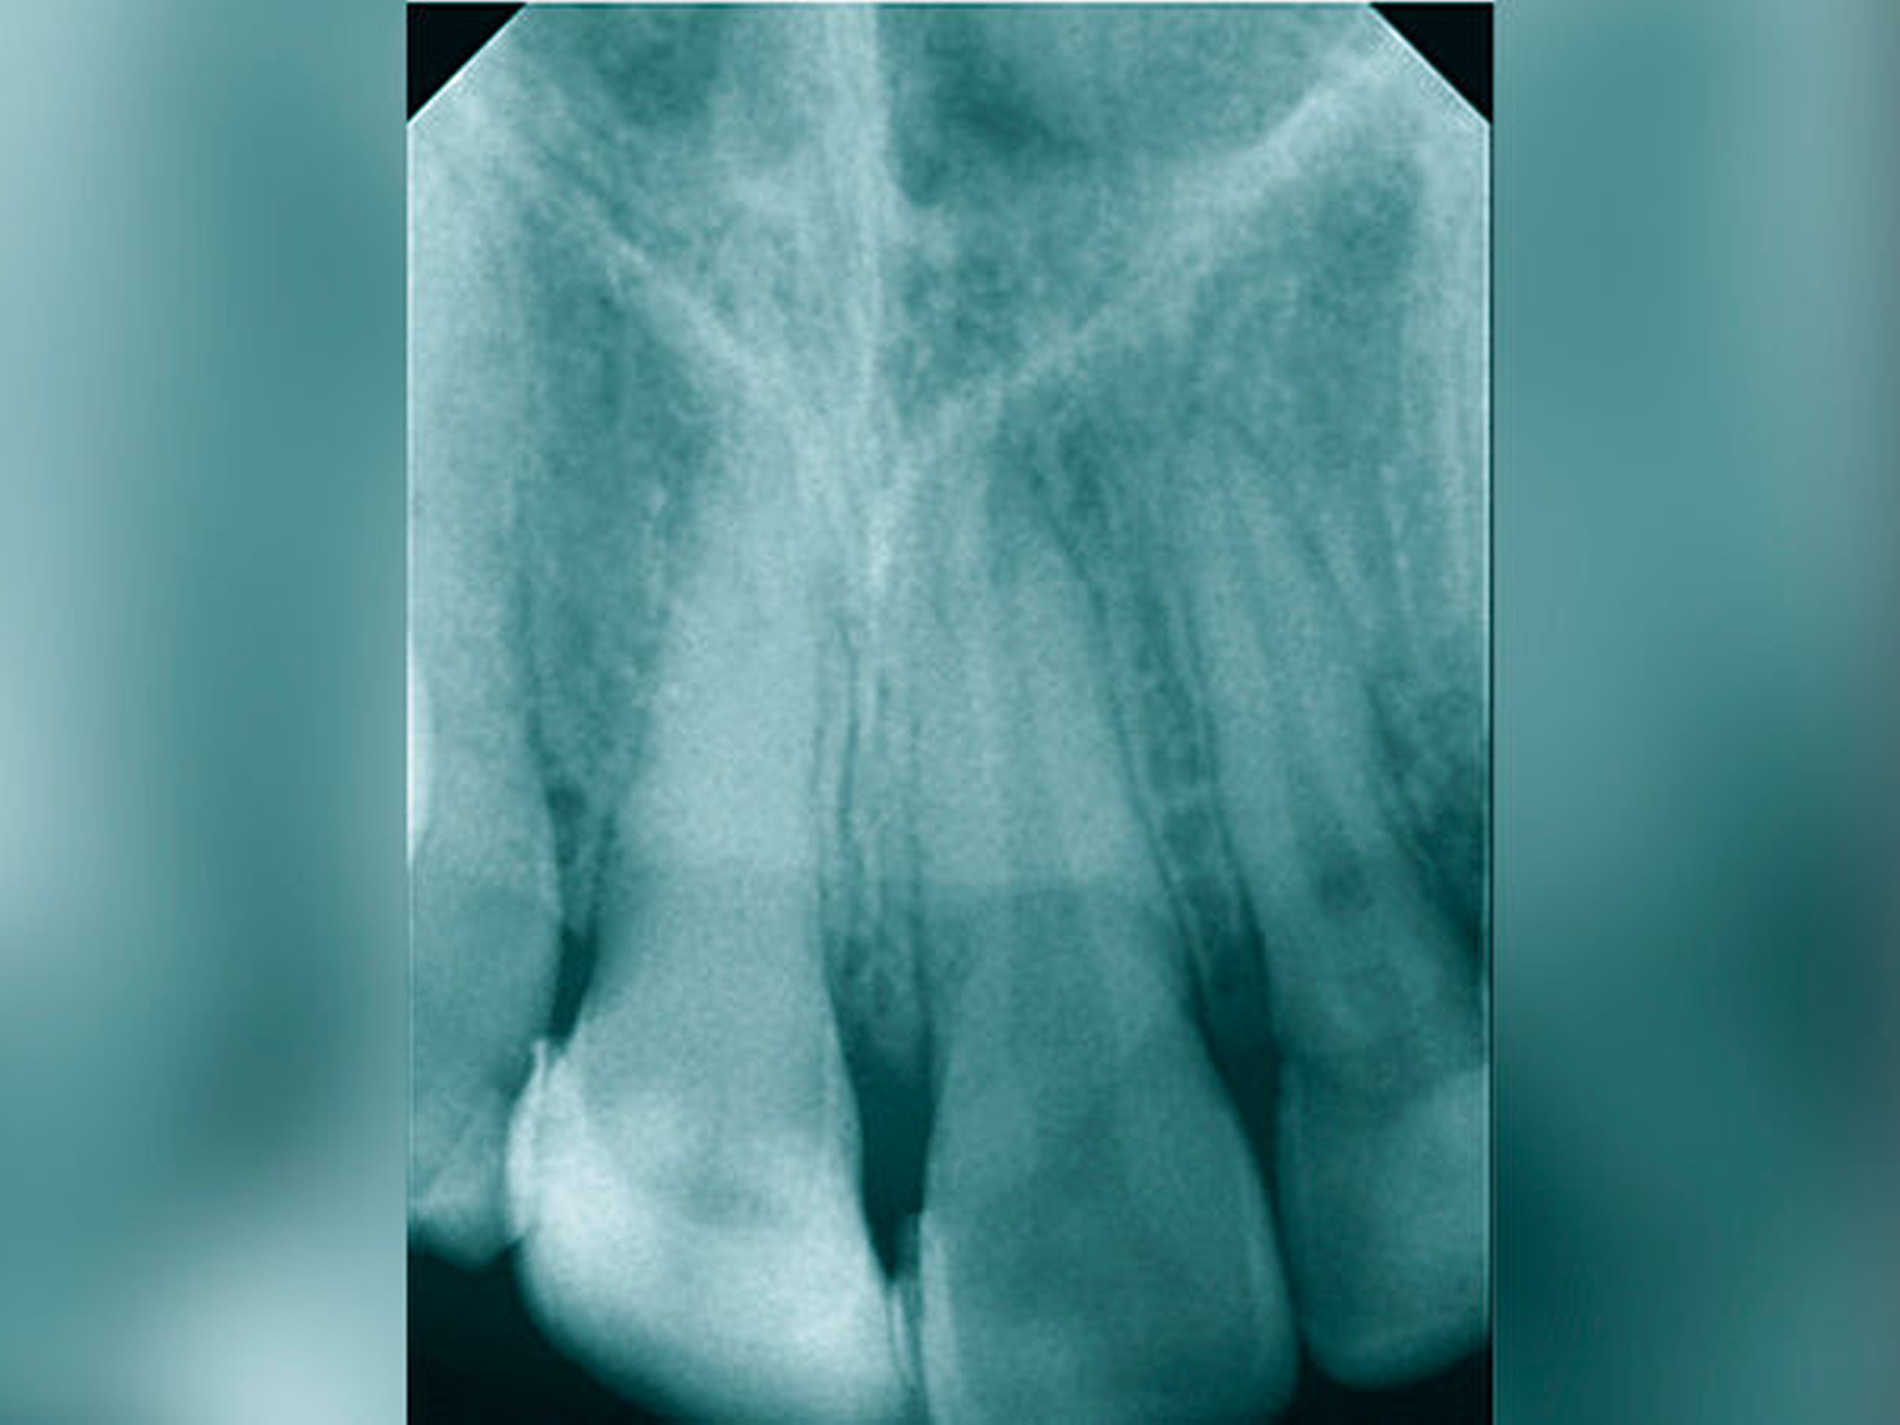

Die Häufigkeit für den Frontzahnverlust beträgt drei bis vier Prozent. Die Altersgipfel liegen zwischen dem achten und dem neunten sowie vom zwölften bis zum 14. Lebensjahr. Betroffene Zähne sind der mittlere und der seitliche Schneidezahn im Oberkiefer. Es besteht eine Korrelation der Häufigkeit zu den Zahnstellungsanomalien der vergrößerten sagittalen Schneidekantenstufe, dem schmalen Deckbiss mit protrudierten seitlichen Schneidezähnen und progen stehenden Einzelzähnen. Obwohl bei Avulsion die sofortige Reimplantation zum Erhalt des Zahnes führen kann, sind häufig Ankylosen des Parodonts und Wurzelresorptionen mit begrenzter Erhaltungswürdigkeit die Folgen. Eine fehlende Sensibilität, ein hoher Klopfschall und der röntgenologische Resorptionsnachweis sind diagnostische Anzeichen dafür.

Erfolglose Reimplantation (Wurzelresorption und Lockerung)

Fehlender Abschluss des Wurzelwachstums, weites Foramen apikale und Avitalität. Eine endodontische Aufbereitung ist aufgrund des divergierenden Wurzelkanals schwierig.